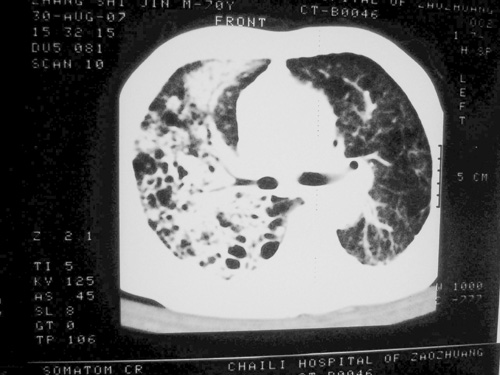

老年男性,70岁。煤矿工人20年。一周前咳嗽、发烧,拍x片考虑矽肺可能。始终咳嗽行ct检查,发现弥漫性病变,似感染但密度很高,细支气管肺泡癌无法排除,请老师给予指点。

一般矽肺多为双肺融合状,团块状高密度结节影.并散在多处小结节影.可这个病人只表现在单肺,并没有融合结节影.一周前的x片没显示大片高密度影,可定位扫描时(图象忽略传了),右肺已经清晰显示大片高密度影.作比较感觉是新病灶.可实际表现又不象,所以才拿来让各位老师看看.

矽肺,两肺间实质炎症,蜂窝肺。

矽肺  两肺间质性炎症伴纤维化(蜂窝肺)

患者病程较短,有明显咳嗽发热症状,结合病史考虑矽肺合并以间质为主的肺感染,肺泡癌先放下,抗炎再说